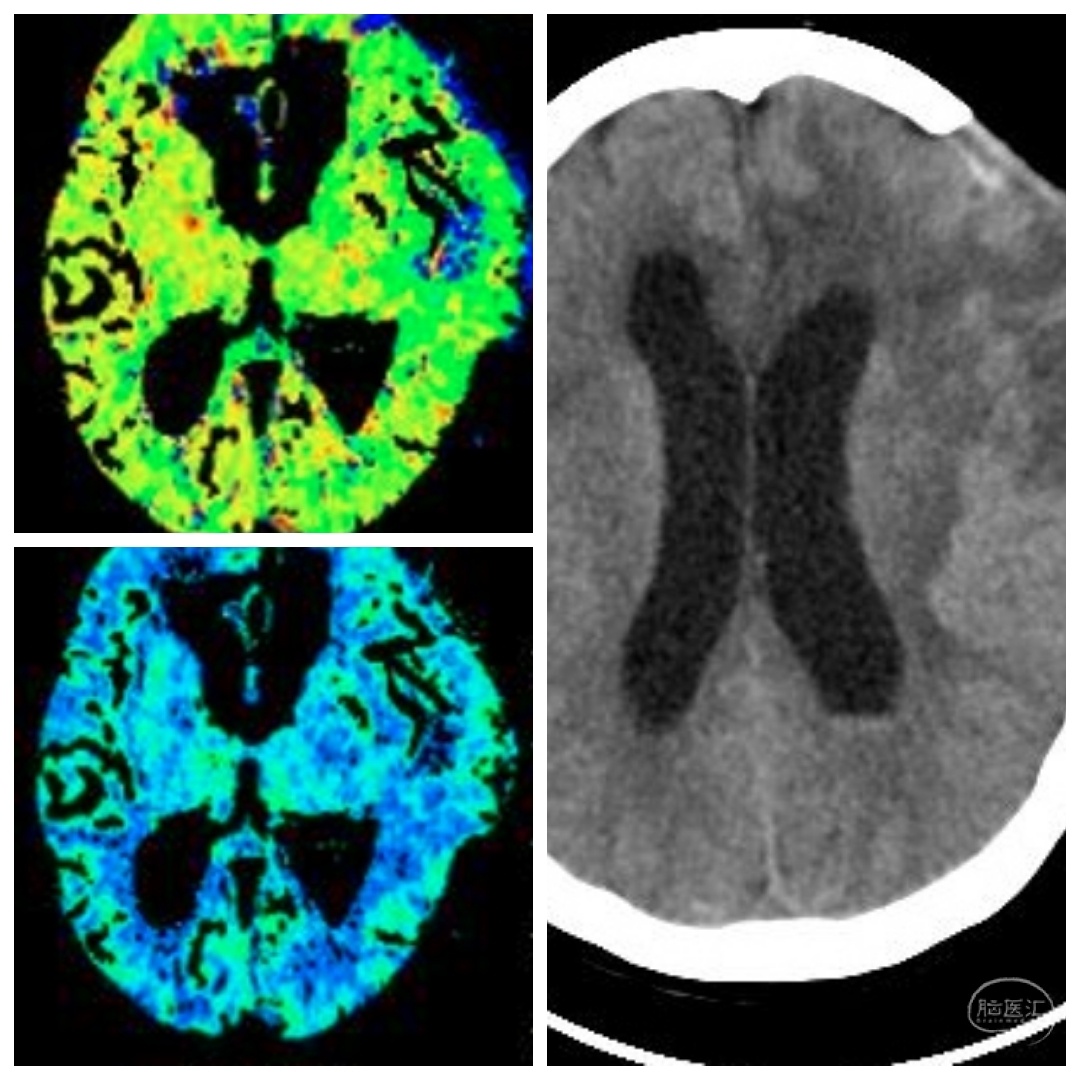

CT及CTA提示左侧大脑灌注不足,左侧大脑中动脉M1狭窄。考虑此处串通支较多,予以搭桥手术。